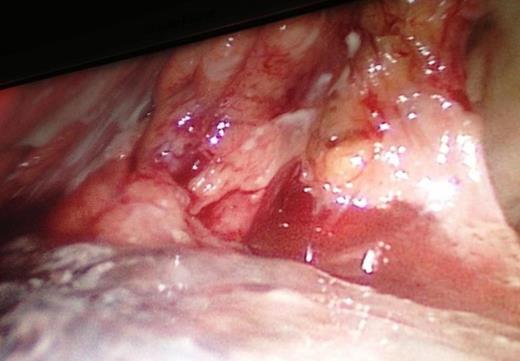

The intraoperative extension of the pancreatic necrosis that involves the entire gland.

Our patient's clinical deterioration precluded the use of preoperative ERCP/MRCP. Clinical suspicion for hollow viscus injury prompted diagnostic laparoscopy. Necrotic and hemorrhagic pancreas precluded any intraoperative attempt to accurately characterize extent of ductal injury. Looking retrospectively, we acknowledge that, if we were able to diagnose ductal transection pre/intraoperatively, our management would have drastically deferred towards distal pancreatectomy.

In addition to being an exploratory, laparoscopy can be effectively used to characterize pancreatic injuries (grading) that informs the management with immediate drainage for the proximal pancreatic part or the resection of the distal injuries, whenever indicated [10]. Therefore, a laparoscopic approach provides a genuine alternative to the open abdominal surgery.